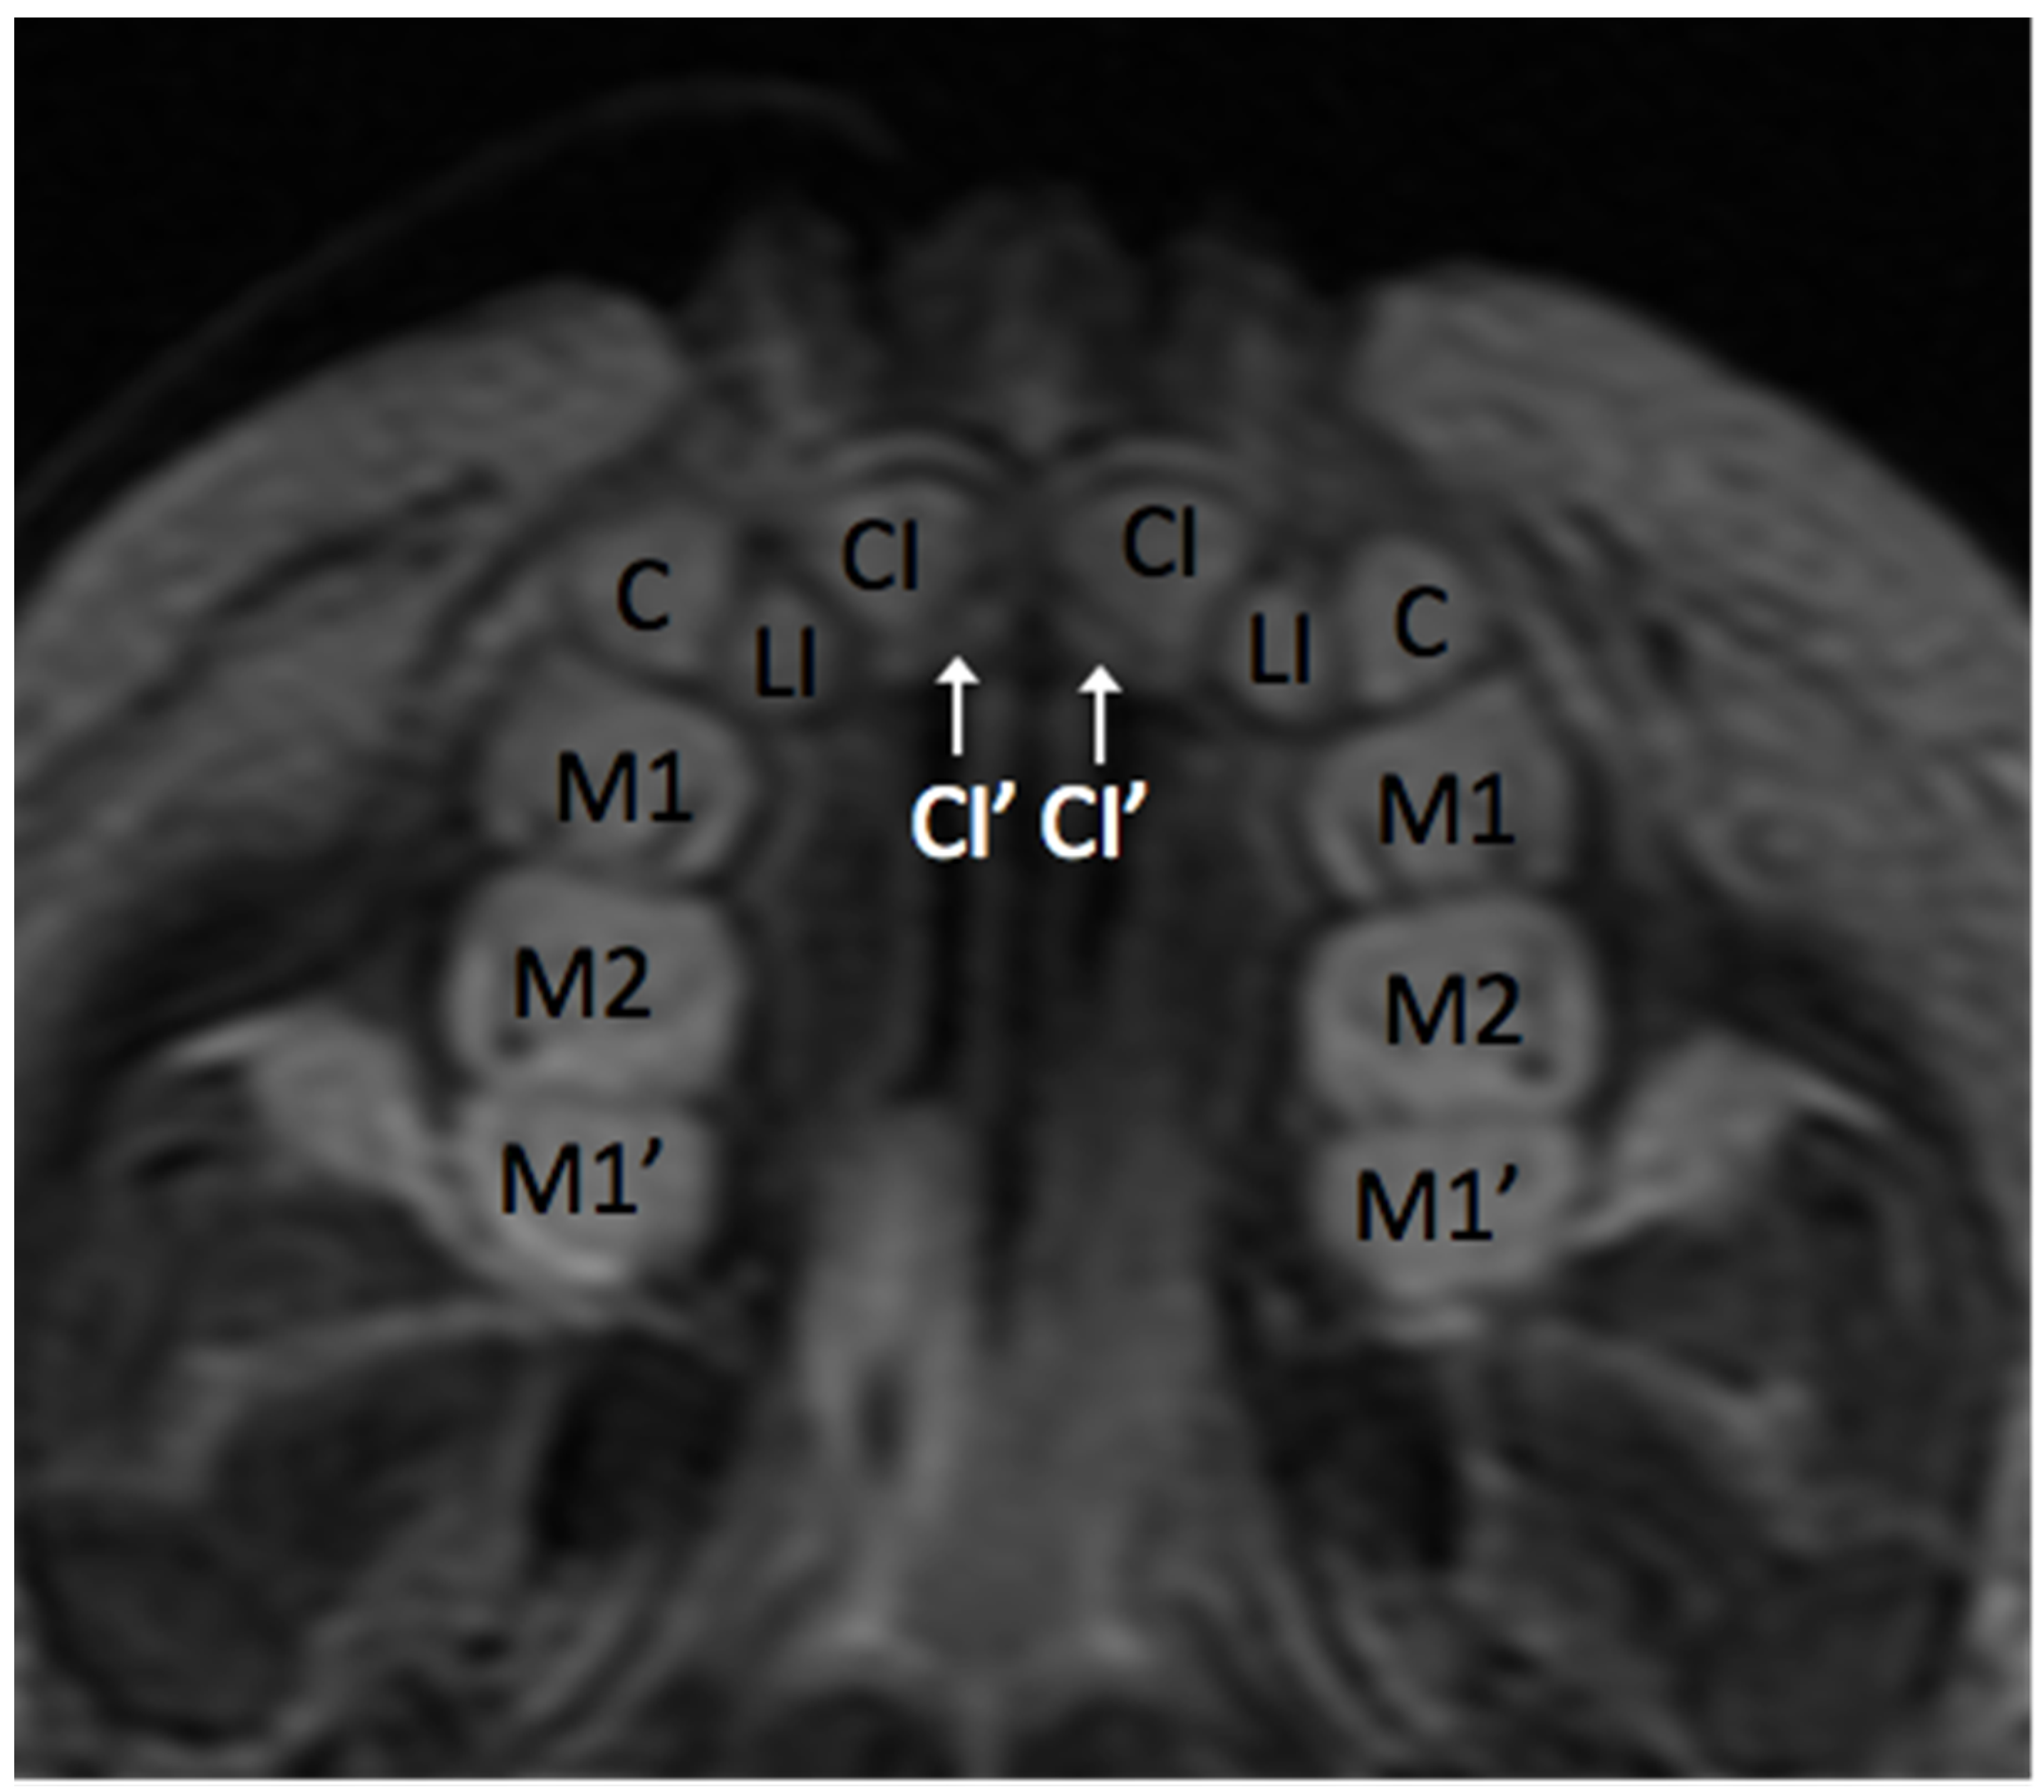

3.1. Anatomy of the Dental Arch

3.4. Application of Principles to Consecutive MR Exams